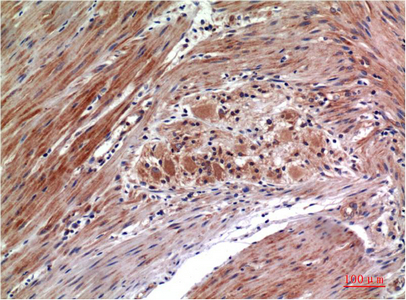

Main InformationTargetERK 1/2Host SpeciesMouseReactivityHuman, Rat, MouseApplicationsIHC, IFMW44,42kD (Observed)Conjugate/ModificationPhosphoDetailed InformationRecommended Dilution RatioIHC 1:100-200; IF 1:50-200FormulationLiquid in PBS containing 50% glycerol, 0.5% BSA and 0.02% sodium azide.SpecificityPhospho-ERK 1/2 (Y222/205)protein detects endogenous levels of MAPK1/MAPK3PurificationThe antibody was affinity-purified from mouse ascites by affinity-chromatography using specific immunogen.Storage-15°C to -25°C/1 year(Do not lower than -25°C)Concentration1 mg/mlMW(Observed)44,42kDModificationPhosphoClonalityMonoclonalClone Number4G3Antigen&Target InformationImmunogen:Synthetic Peptide of Phospho-ERK 1/2 (Y222/205) at AA range of 140-220Specificity:Phospho-ERK 1/2 (Y222/205)protein detects endogenous levels of MAPK1/MAPK3Gene Name:MAPK1/MAPK3Protein Name:MAPK1/MAPK3Other Name:MAPK1/MAPK3Background:The protein encoded by this gene is a member of the MAP kinase family. MAP kinases, also known as extracellular signal-regulated kinases (ERKs), act in a signaling cascade that regulates various cellular processes such as proliferation, differentiation, and cell cycle progression in response to a variety of extracellular signals. This kinase is activated by upstream kinases, resulting in its translocation to the nucleus where it phosphorylates nuclear targets. Alternatively spliced transcript variants encoding different protein isoforms have been described. [provided by RefSeq, Jul 2008],Function:Catalytic activity:ATP + a protein = ADP + a phosphoprotein.,cofactor:Magnesium.,Domain:The TXY motif contains the threonine and tyrosine residues whose phosphorylation activates the MAP kinases.,enzyme regulation:Activated by tyrosine phosphorylation in response to insulin and NGF.,Function:Involved in both the initiation and regulation of meiosis, mitosis, and postmitotic functions in differentiated cells by phosphorylating a number of transcription factors such as ELK-1. Phosphorylates EIF4EBP1; required for initiation of translation. Phosphorylates microtubule-associated protein 2 (MAP2). Phosphorylates SPZ1 (By similarity). Phosphorylates heat shock factor protein 4 (HSF4).,PTM:Dually phosphorylated on Thr-202 and Tyr-204, which activates the enzyme.,similarity:Belongs to the protein kinase superfamily.,similarity:Belongs to the protein kinase superfamily. CMGC Ser/Thr protein kinase family. MAP kinase subfamily.,similarity:Contains 1 protein kinase domain.,subunit:Interacts with MORG1 (By similarity). Binds to HIV-1 Nef. This interaction inhibits its kinase activity. Interacts with HSF4 and NISCH.,Cellular Localization:Cytoplasm . Nucleus. Membrane, caveola . Cell junction, focal adhesion . Autophosphorylation at Thr-207 promotes nuclear localization (PubMed:19060905). PEA15-binding redirects the biological outcome of MAPK3 kinase-signaling by sequestering MAPK3 into the cytoplasm (By similarity). .Tissue Expression:Epithelium,Eye,Hepatoma,Human cervix,Lymph,Research Areas:>>EGFR tyrosine kinase inhibitor resistance ; >>Endocrine resistance ; >>Platinum drug resistance ; >>MAPK signaling pathway ; >>ErbB signaling pathway ; >>Ras signaling pathway ; >>Rap1 signaling pathway ; >>cGMP-PKG signaling pathway ; >>cAMP signaling pathway ; >>Chemokine signaling pathway ; >>HIF-1 signaling pathway ; >>FoxO signaling pathway ; >>Sphingolipid signaling pathway ; >>Phospholipase D signaling pathway ; >>Oocyte meiosis ; >>Autophagy - animal ; >>mTOR signaling pathway ; >>PI3K-Akt signaling pathway ; >>Apoptosis ; >>Cellular senescence ; >>Adrenergic signaling in cardiomyocytes ; >>Vascular smooth muscle contraction ; >>TGF-beta signaling pathway ; >>Axon guidance ; >>VEGF signaling pathway ; >>Apelin signaling pathway ; >>Osteoclast differentiation ; >>Focal adhesion ; >>Adherens junction ; >>Gap junction ; >>Signaling pathways regulating pluripotency of stem cells ; >>Platelet activation ; >>Neutrophil extracellular trap formation ; >>Toll-like receptor signaling pathway ; >>NOD-like receptor signaling pathway ; >>C-type lectin receptor signaling pathway ; >>Natural killer cell mediated cytotoxicity ; >>IL-17 signaling pathway ; >>Th1 and Th2 cell differentiation ; >>Th17 cell differentiation ; >>T cell receptor signaling pathway ; >>B cell receptor signaling pathway ; >>Fc epsilon RI signaling pathway ; >>Fc gamma R-mediated phagocytosis ; >>TNF signaling pathway ; >>Circadian entrainment ; >>Long-term potentiation ; >>Neurotrophin signaling pathway ; >>Retrograde endocannabinoid signaling ; >>Glutamatergic synapse ; >>Cholinergic synapse ; >>Serotonergic synapse ; >>Long-term depression ; >>Regulation of actin cytoskeleton ; >>Insulin signaling pathway ; >>GnRH signaling pathway ; >>Progesterone-mediated oocyte maturation ; >>Estrogen signaling pathway ; >>Melanogenesis ; >>Prolactin signaling pathway ; >>Thyroid hormone signaling pathway ; >>Oxytocin signaling pathway ; >>Relaxin signaling pathway ; >>Parathyroid hormone synthesis, secretion and action ; >>GnRH secretion ; >>Type II diabetes mellitus ; >>AGE-RAGE signaling pathway in diabetic complications ; >>Cushing syndrome ; >>Growth hormone synthesis, secretion and action ; >>Aldosterone-regulated sodium reabsorption ; >>Alzheimer disease ; >>Prion disease ; >>Pathways of neurodegeneration - multiple diseases ; >>Alcoholism ; >>Pathogenic Escherichia coli infection ; >>Shigellosis ; >>Salmonella infection ; >>Pertussis ; >>Yersinia infection ; >>Leishmaniasis ; >>Chagas disease ; >>Toxoplasmosis ; >>Tuberculosis ; >>Hepatitis C ; >>Hepatitis B ; >>Human cytomegalovirus infection ; >>Influenza A ; >>Human papillomavirus infection ; >>Human T-cell leukemia virus 1 infection ; >>Kaposi sarcoma-associated herpesvirus infection ; >>Human immunodeficiency virus 1 infection ; >>Coronavirus disease - COVID-19 ; >>Pathways in cancer ; >>Viral carcinogenesis ; >>Proteoglycans in cancer ; >>MicroRNAs in cancer ; >>Chemical carcinogenesis - receptor activation ; >>Chemical carcinogenesis - reactive oxygen species ; >>Colorectal cancer ; >>Renal cell carcinoma ; >>Pancreatic cancer ; >>Endometrial cancer ; >>Glioma ; >>Prostate cancer ; >>Thyroid cancer ; >>Melanoma ; >>Bladder cancer ; >>Chronic myeloid leukemia ; >>Acute myeloid leukemia ; >>Non-small cell lung cancer ; >>Breast cancer ; >>Hepatocellular carcinoma ; >>Gastric cancer ; >>Central carbon metabolism in cancer ; >>Choline metabolism in cancer ; >>PD-L1 expression and PD-1 checkpoint pathway in cancer ; >>Lipid and atherosclerosis